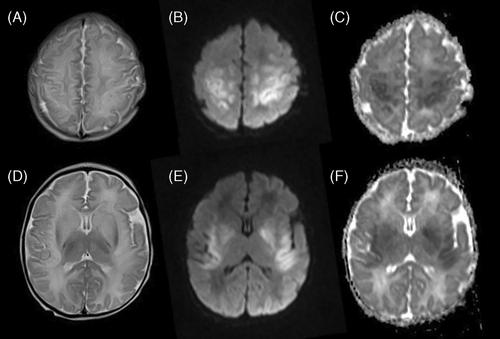

Carbonic anhydrase VA (CA-VA) deficiency is a rare cause of hyperammonemia caused by biallelic mutations in CA5A. Most patients present with hyperammonemic encephalopathy in early infancy to early childhood, and patients usually have no further recurrence of hyperammonemia with a favorable outcome. This retrospective cohort study reports 18 patients with CA-VA deficiency caused by homozygosity for a founder mutation, c.59G>A p.(Trp20*) in CA5A. The reported patients show significant intrafamilial and interfamilial variability, and display atypical clinical features. Two adult patients were asymptomatic, 7/18 patients had recurrent hyperammonemia, 7/18 patients developed variable degree of developmental delay, 9/11 patients had hyperCKemia, and 7/18 patients had failure to thrive. Microcephaly was seen in three patients and one patient developed a metabolic stroke. The same variant had been reported already in a single South Asian patient presenting with neonatal hyperammonemic encephalopathy and subsequent development of seizures and developmental delay. This report highlights the limitations of current understanding of the pathomechanisms involved in this disorder, and calls for further evaluation of the possible role of genetic modifiers in this condition.